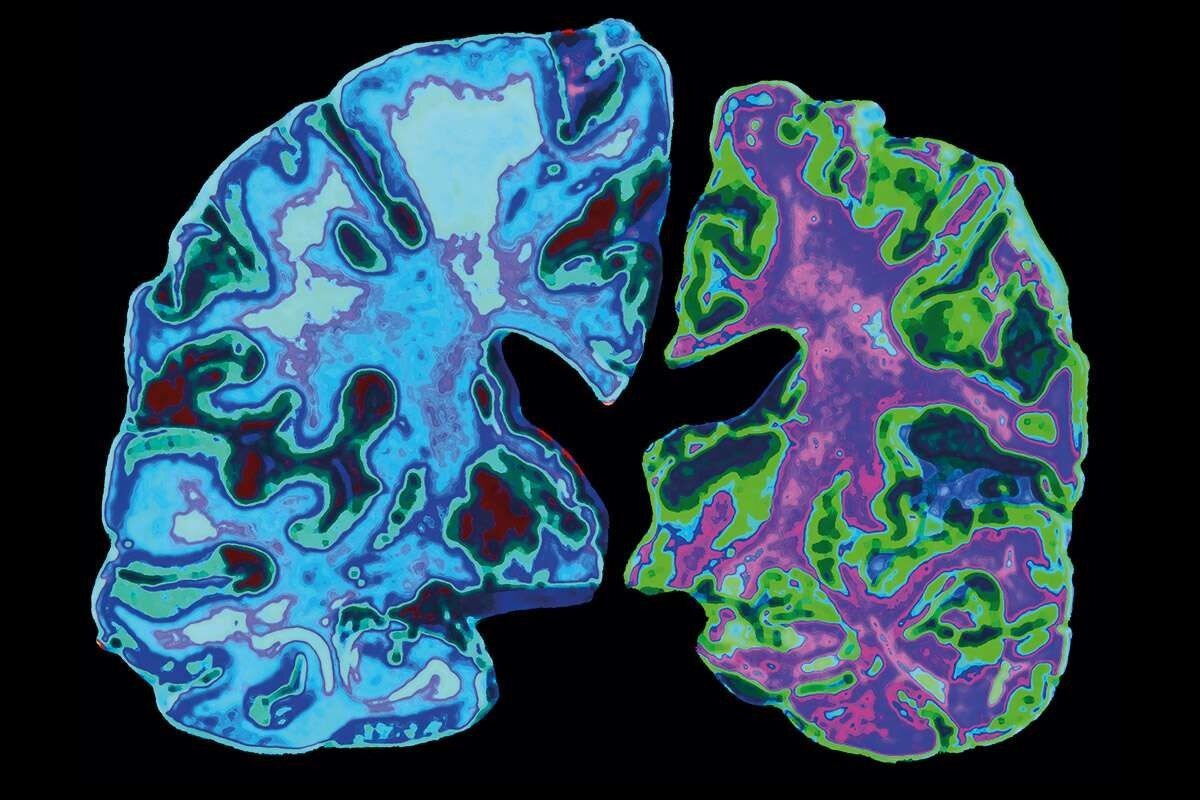

Болезнь Альцгеймера («болезнь стариков») наряду со СПИДом входит в группу заболеваний, не поддающихся лечению. Можно их купировать, ослаблять симптомы, но методов эффективного лечения на сегодняшний день не существует. Помощь придет с не самой очевидной стороны — фармакологии поможет генная инженерия.

Исследования человеческого генома и генетических мутаций приведут к лучшему пониманию таких дегенеративных расстройств, как слабоумие и болезнь Альцгеймера, и созданию способов предотвращения их развития. Сегодняшние достижения ученых уже через десять лет будут иметь далеко идущие последствия.

Текущие исследования нейродегенеративных заболеваний нацелены на выявление патогенных хромосом, которые и приводят к развитию болезни. Подобные знания чрезвычайно ценны для медицины, ведь в перспективе они позволят ученым исправлять генетические отклонения и предотвращать появление старческого слабоумия.

Уже сегодня врачам удается изолировать хромосомы, вызывающие некоторые виды умственных расстройств. А к 2025 году, с улучшением методов диагностики и развитию специализированной медицинской техники, количество страдающих от этих страшных болезней людей может стать меньше.